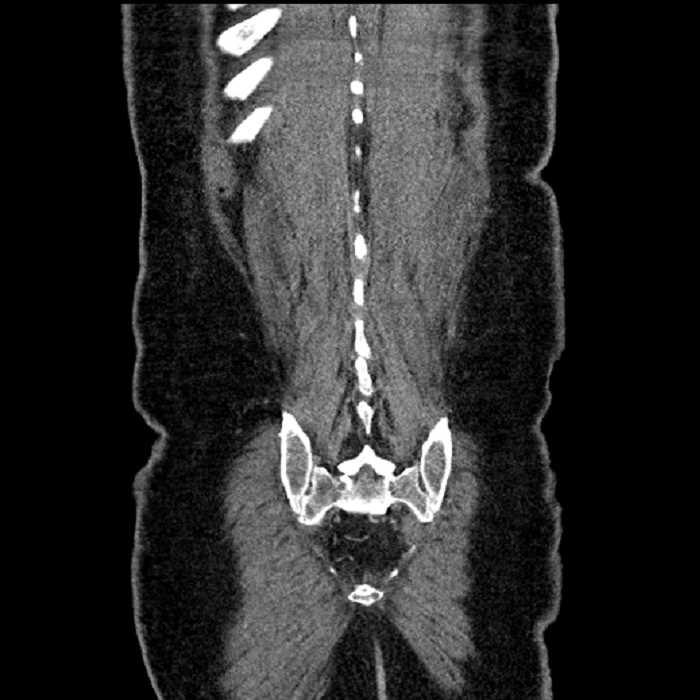

Age: 63

Sex: Male

Indication: Abdominal pain

Findings

• Lower chest

• Mild cardiomegaly

• Mild dependent atelectasis

• Abdomen/Pelvis

• Large fluid density structure in hepatic segments 7 and 8 measuring 10 x 7 x 7 cm with internal septation and circumferential ill-defined low density compatible with edema

• Peripherally enhancing subcapsular collections along the anterior margin of the left hepatic lobe measuring 3 x 1 cm and 2 x 1 cm

• Clearly marginated fluid density structure in segment 7 and several other scattered tiny hypodensities, which likely represent cysts

• Mild mural thickening of a segment of the sigmoid colon with adjacent fat stranding and a 1.5 cm fluid and gas collection along the tip of an inflamed diverticulum

• Loss of the normal fat plane between this collection and adjacent loops of small bowel, which demonstrate mural thickening

• No bowel obstruction

• High grade stenosis of the left common iliac artery, with the left internal and external iliac arteries remaining patent

• Incidental splenule

• MSK

• No acute findings

• Ankylosis of both sacroiliac joints

• Circumscribed sclerotic lesion in the left anterolateral seventh rib without aggressive features, likely a bone island

Diagnosis

• Hepatic abscess

Acute sigmoid diverticulitis complicated by a small contained perforation and a large abscess in the right hepatic lobe. Additional small subcapsular abscesses along the anterior margin of the left hepatic lobe.

Additionally, loss of the normal fat plane between the peridiverticular collection and adjacent thickened loops of small bowel raises the potential for an enterocolonic fistula.

High grade stenosis of the left common iliac artery. The left external and internal iliac arteries are patent.